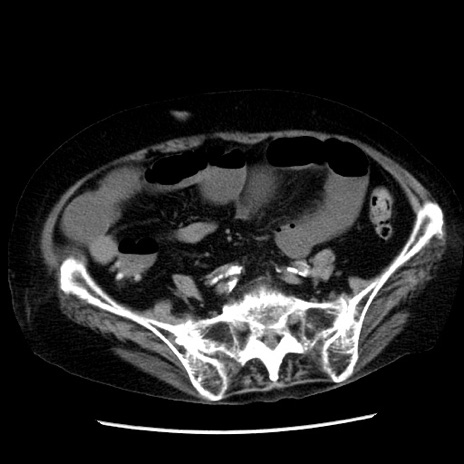

冠状断像

症例14(横断像)

【症例】 90歳代女性

【主訴】 腹痛・嘔吐

【現病歴】今朝から左側腹部痛を認めた。 経過観察していたが、嘔吐を認めたため来院。

【既往歴】 子宮癌術後

【身体所見】 意識清明、BP 127/54mmHg、P 98bpm Sp02 95%(RA)、BT 35.8°C、腹部平坦・軟腸ぜん動音聴取良好、右下腹部圧痛(+) 反跳痛なし

【データ】WBC 9800、CRP 0.46